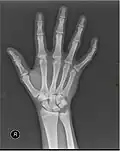

Metacarpals shown in red. Left hand, anterior (palmar) view.

The five metacarpal bones, numbered. Left hand, anterior (palmar) view.